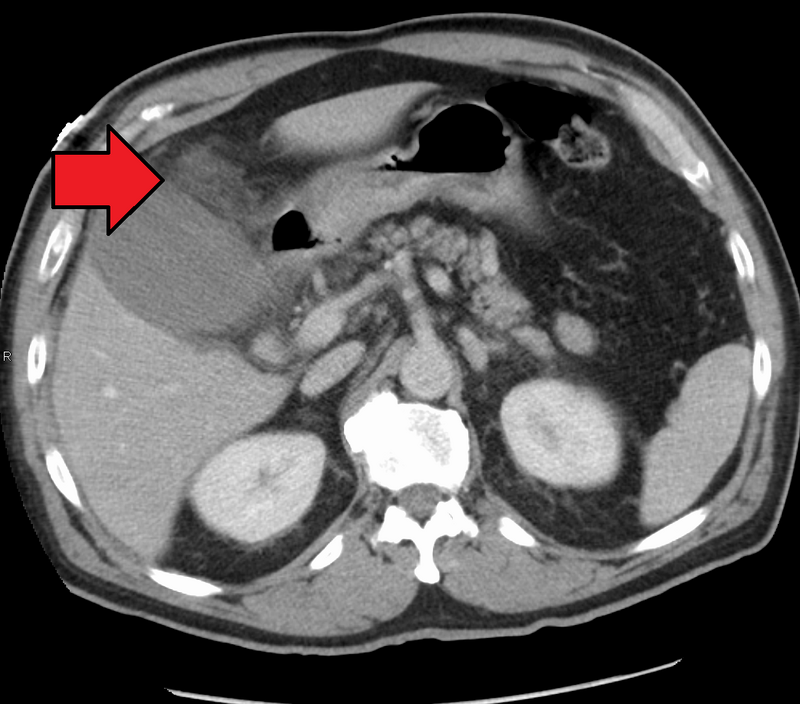

পিত্তথলীর প্রদাহের ছবি

যখন কোন কারণে পিত্তাশয় (Gallbladder)-এর প্রদাহ হলে ডান দিকের উপরের পেটে তীব্র ব্যথা, বমি বমি ভাব, বা বমি হয় এবং মাঝে মাঝে জ্বর হয় প্রভৃতি উপসর্গের সৃষ্টি হয় তখন তাকে পিত্তশলীর প্রদাহ (Cholecystitis) বলে। অর্থাৎ পিত্তথলীর প্রদাহকে Cholecystitis বলে।

• CT Scan.